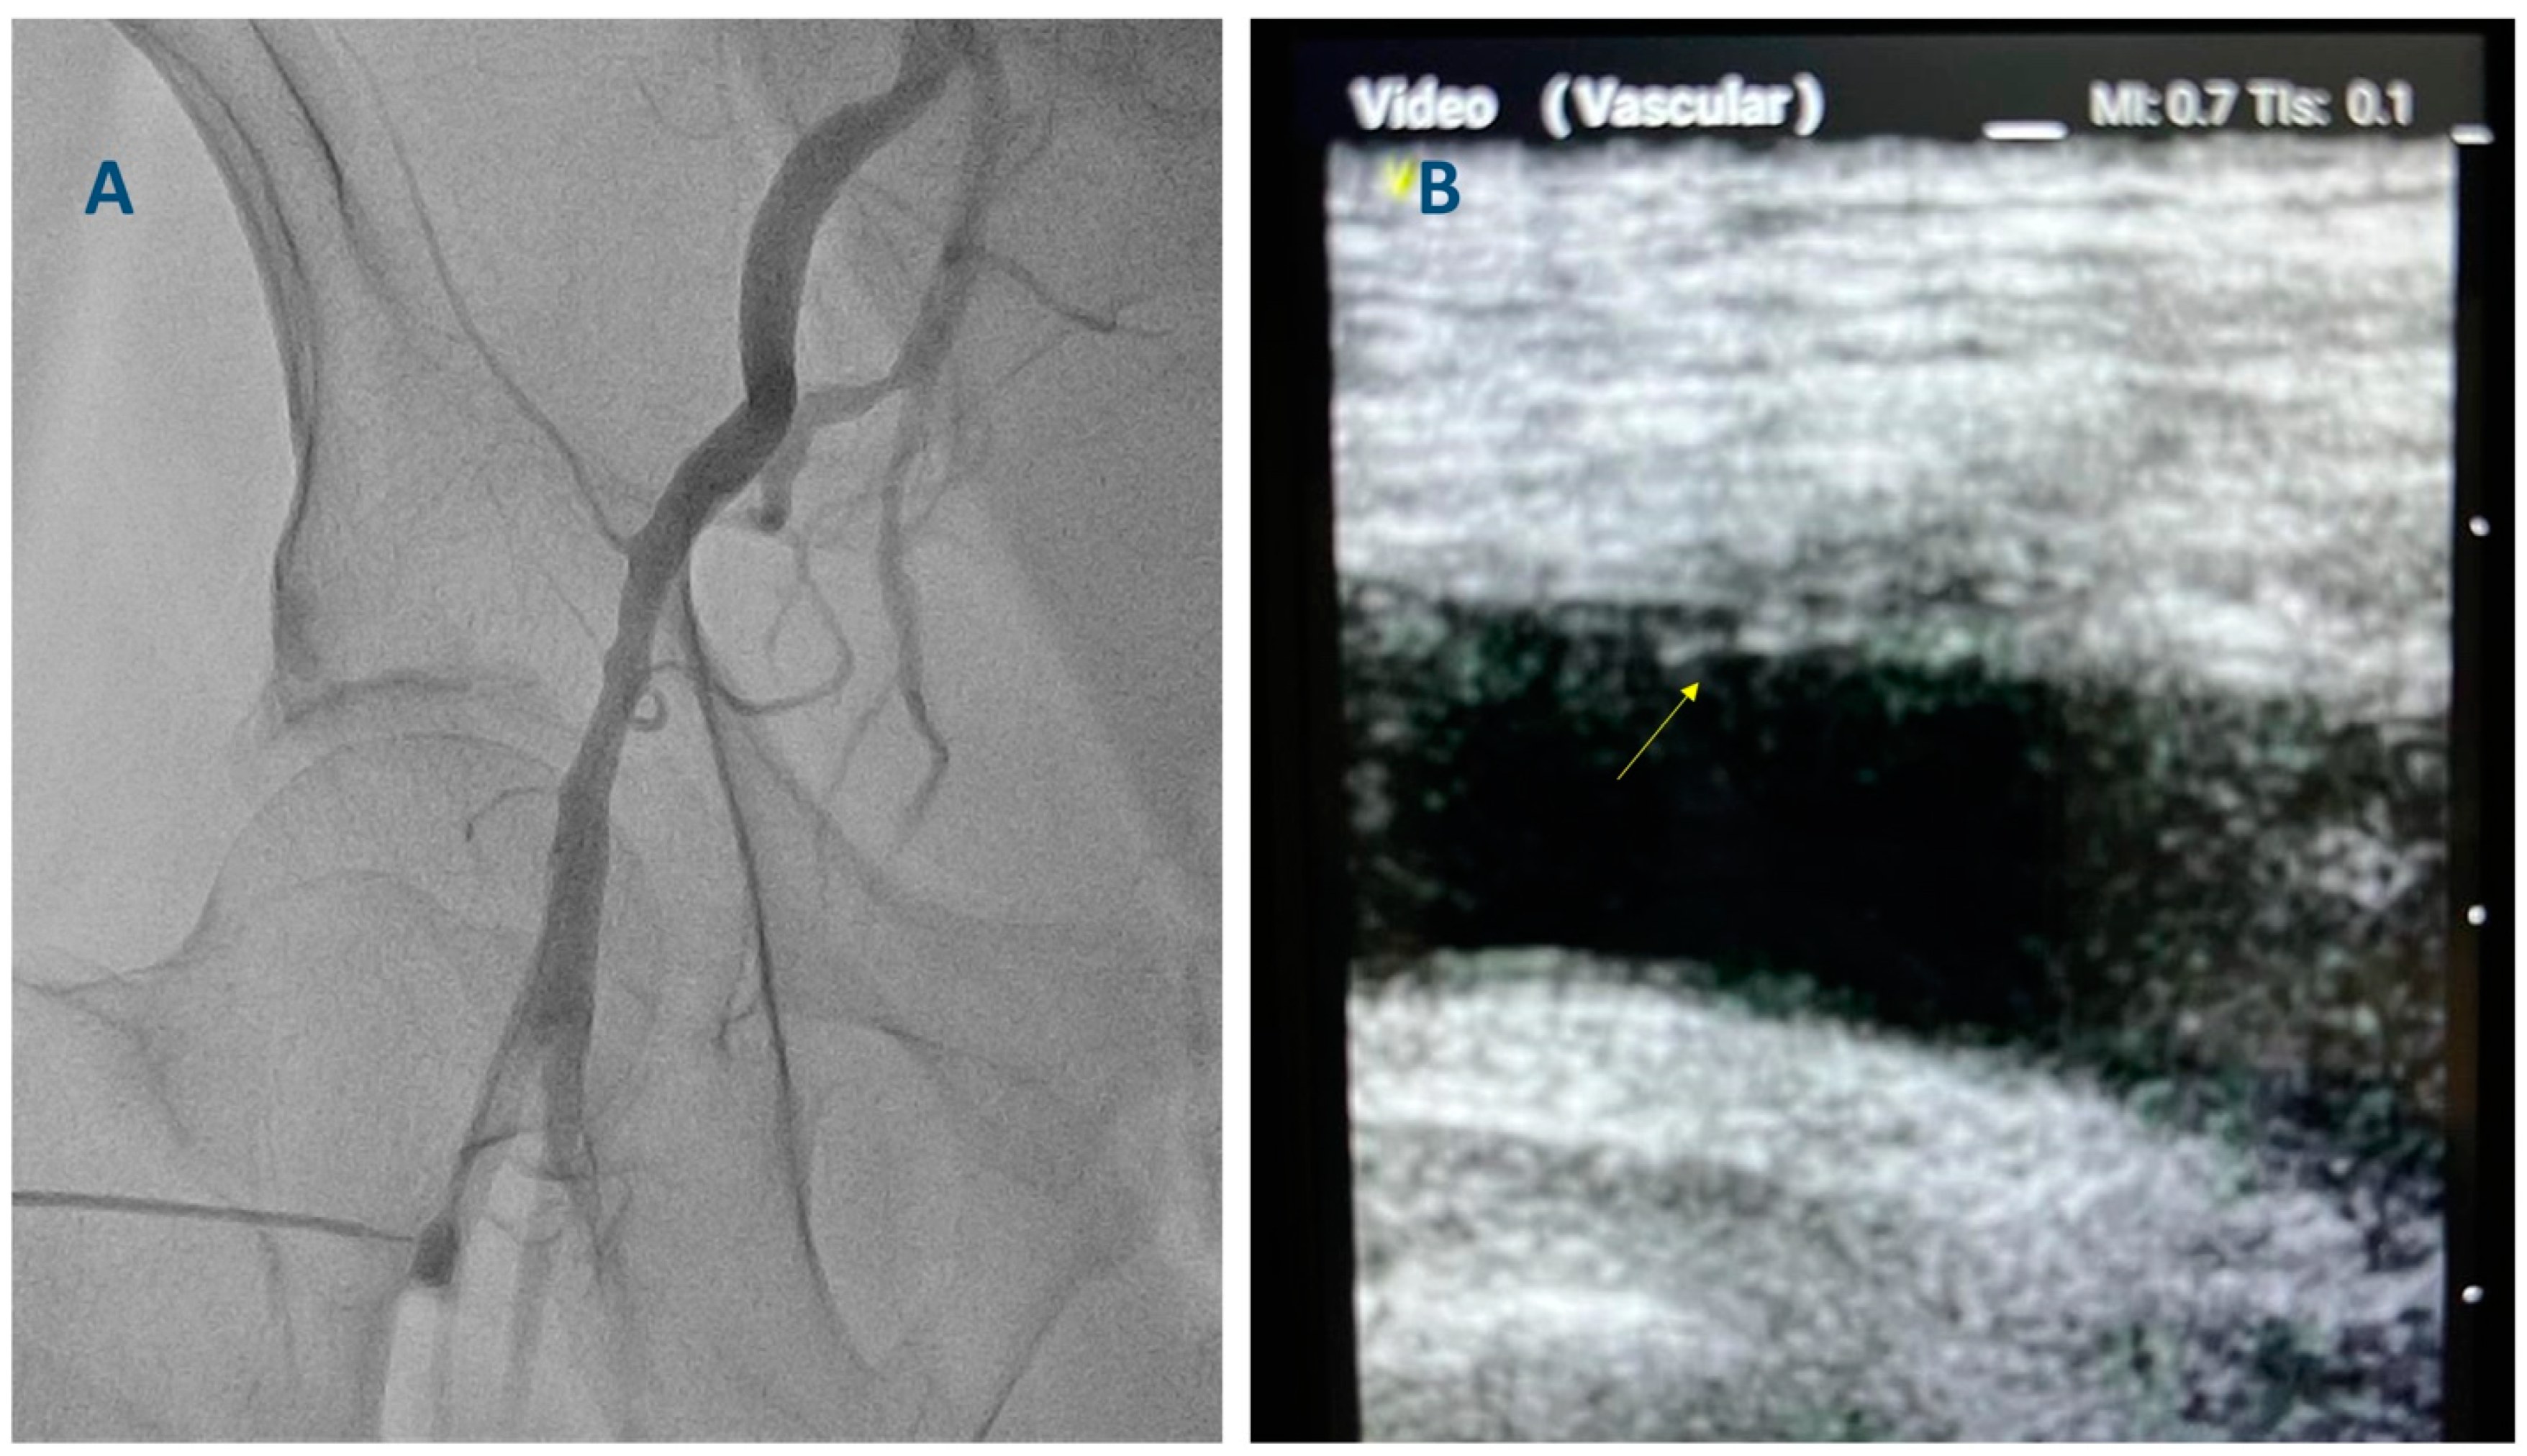

2. Existing Evidence Supporting the Use of Ultrasound-Guided Femoral Access